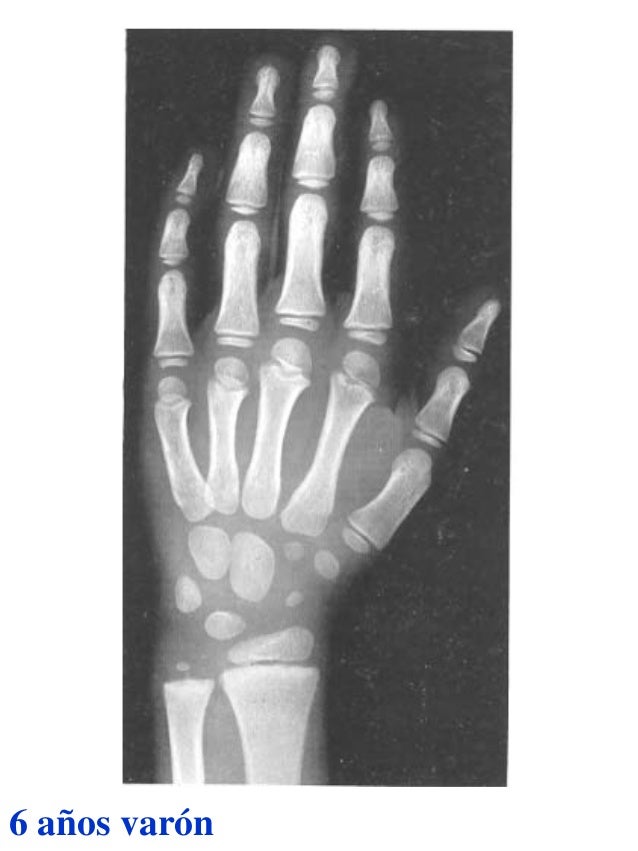

Figura 2 Imágenes de radiografías de mano y muñeca izquierda del

Figura 2 Imágenes de radiografías de mano y muñeca izquierda del Tablas De Greulich Y Pyle Edad Osea The greulich and pyle atlas is used to estimate the age of children and adolescents. El método de greulich y pyle(1) es un método simple de valoración de la edad ósea en pacientes pediátricos. El diagnóstico y la clasificación se basan en el examen físico, el análisis del crecimiento, la maduración ósea, la ecografía de útero y gónadas, y los. Tablas De Greulich Y Pyle Edad Osea.